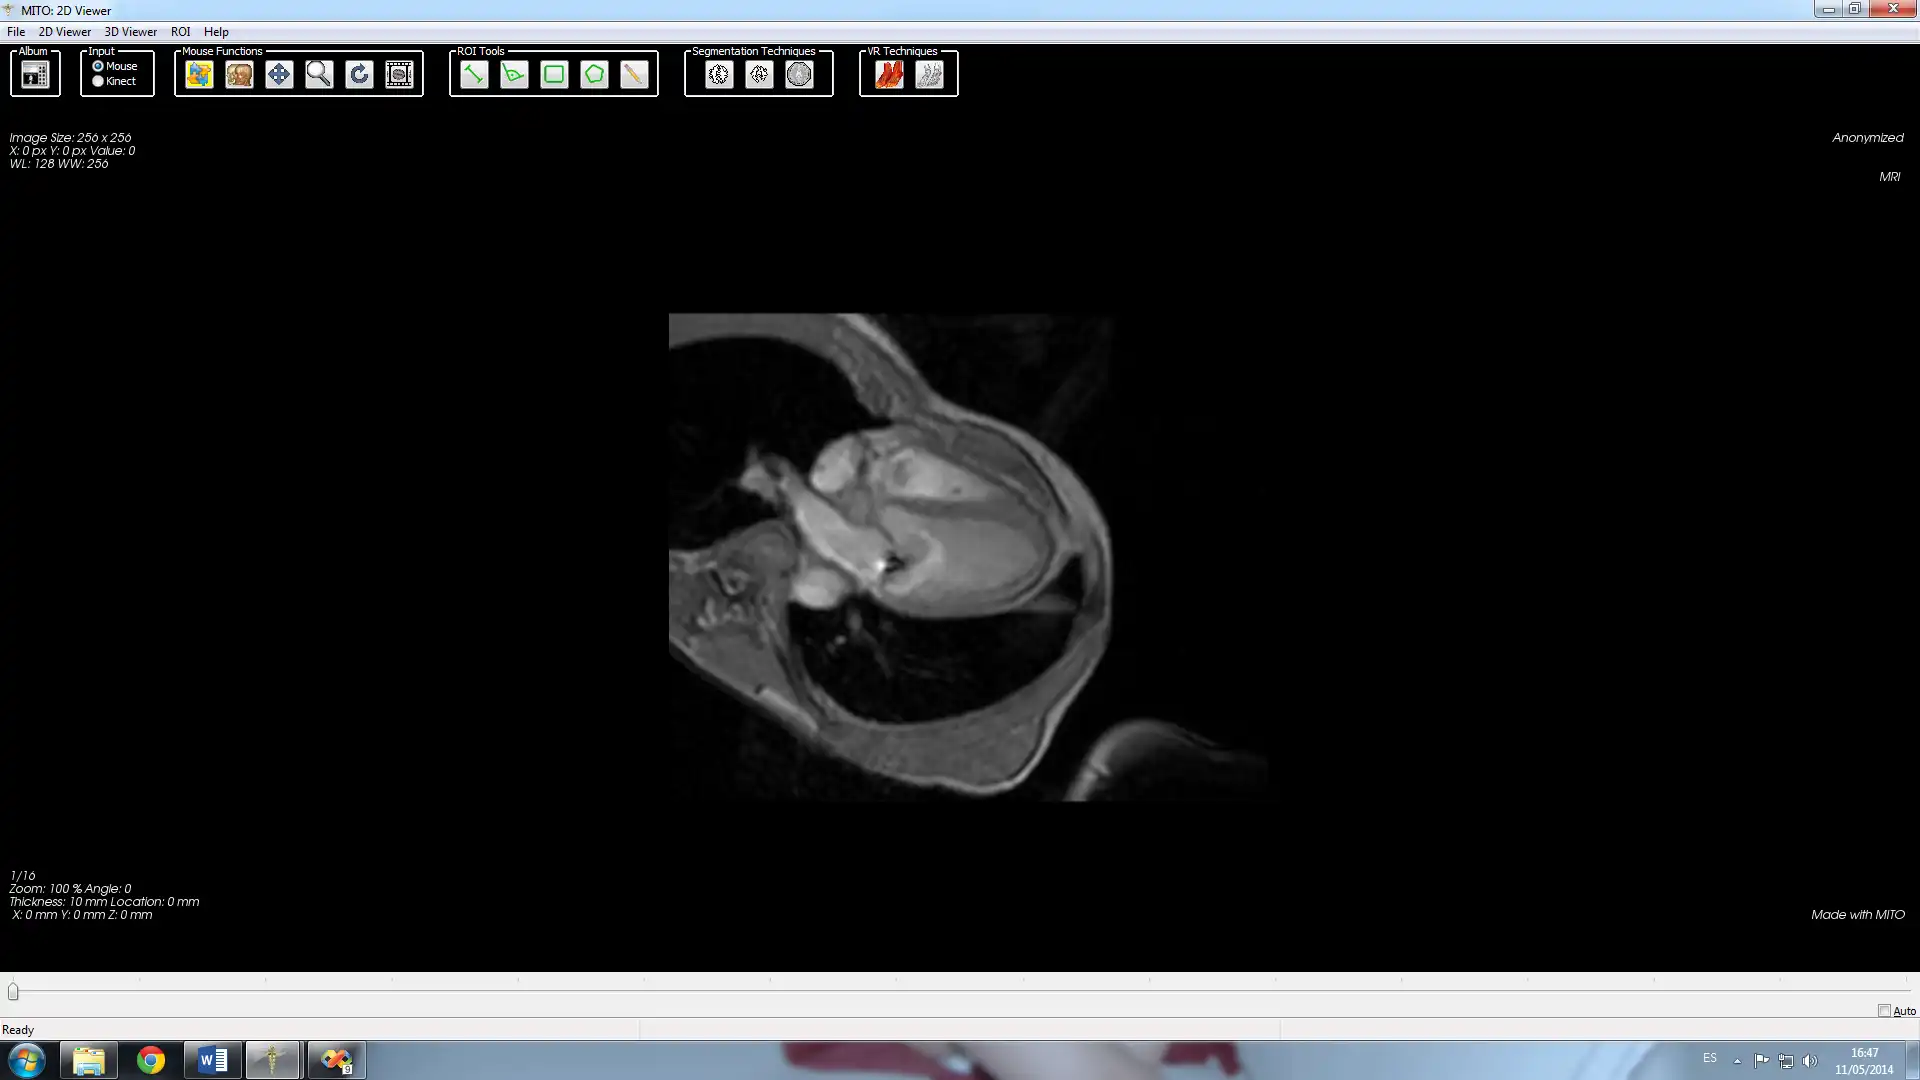

MITO - Leap Motion - Fork to run in Windows online over Linux online

MITO Leap Motion Fork is a fork of the Medical Imaging TOolkit. It integrate the Leap SDK so that you can interact with the application using hand gestures.Features

- DICOM compliant

- 2D / 3D / S3D visualization

- manual / automatic image segmentation and fusion

- advanced 3D user interfaces

- PACS connectivity

- Leap Motion